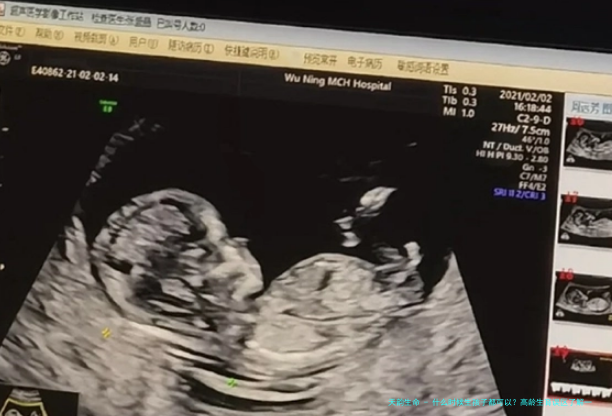

在临床上,过了35岁之上的女性怀孕则被称作为高龄孕妇。因为当女性到了35岁将来,肌体身在下滑走势,先天性胎儿缺陷的产生率增加,高龄产妇合并症的风险同样会增加。

三、高龄孕妇临盆只可选择剖宫产

许许多多人都说高龄孕妇不可正常分娩,实际上不一定。女性在分娩此前会都做产前筛查,只要是已经达到正常分娩的先决条件,纵然高龄也能够自然分娩。一般情况,40岁将来头一次分娩的孕妇,才相较合适第一选择剖宫产,而并不是是所有高龄孕妇都必要抉择手术分娩。